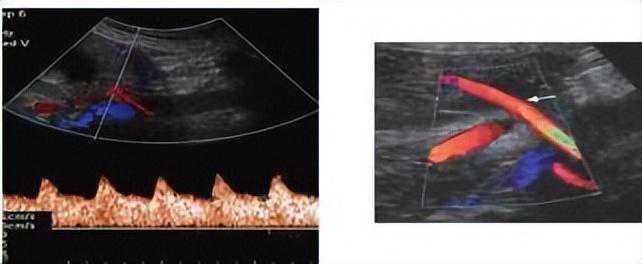

3.超声多普勒监测子宫动脉血流及舒张早期切迹等指标

子宫动脉血流速度波形主要用于估测子宫-胎盘循环。妊娠中期子宫动脉阻力指数升高、持续性子宫动脉舒张期早期切迹说明胎盘母体面血流减少,与子痫前期的发生有关。